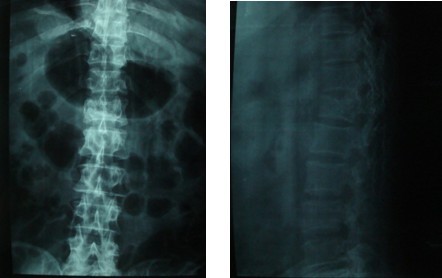

患者,男性,56岁, 因车祸伤致腰痛、胸痛、骨盆痛6小时来我院就诊。患者2009-11-8被汽车撞伤腰部,当时双下肢不能活动,伴头晕、大汗,无明显外出血,就诊于当地医院,查血压70/50mmHg,诊断为“多发伤,休克”,予抗休克治疗,X线和CT检查示“胸12椎体爆裂骨折、腰2-4右侧横突骨折(见图1、图2);右肩胛骨骨折(见图3、图4);多发肋骨骨折、右侧血胸(见图5);右耻骨上下支粉碎性骨折、右髂骨骨折合并右骶髂关节半脱位(见图6、图7)”。

图1、图2 正侧位X线片示T12爆裂骨折、L2-4右侧横突骨折